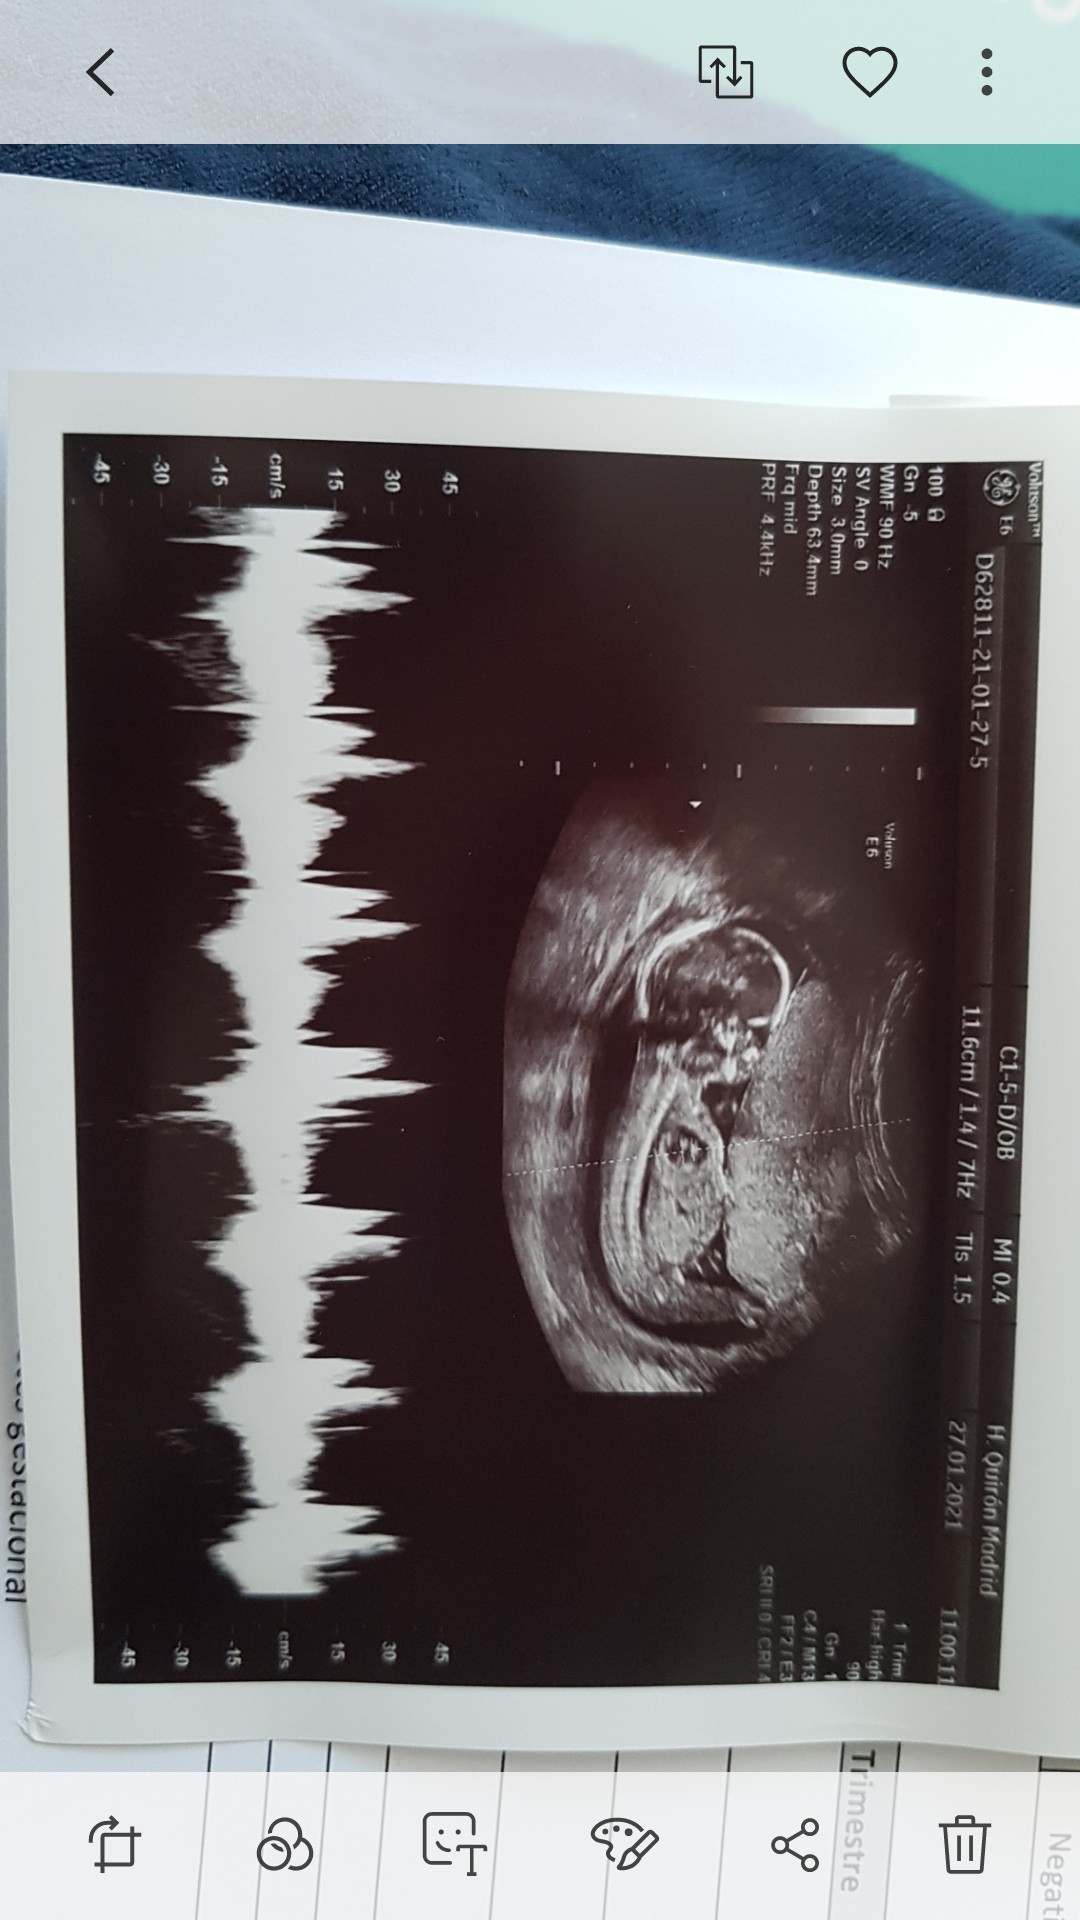

My już po wizycie 16+3 Wiktoria jest nadal Wiktoria .

Szyjka 2.5 .... dostałam 600 utrogestan I kontrola 03.02 I 10.02